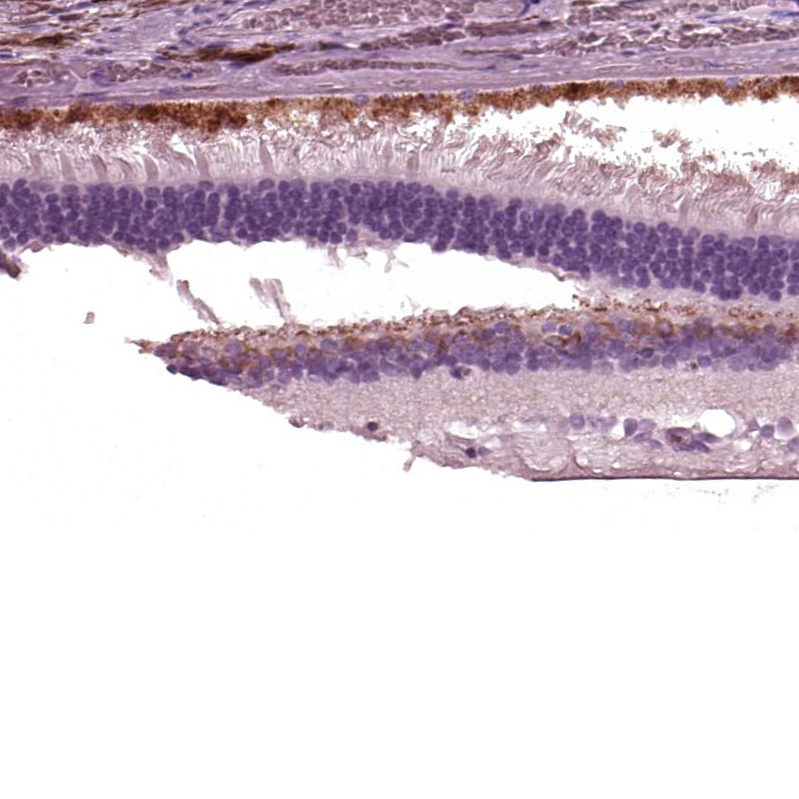

Immunohistochemical staining of human retina shows strong cytoplasmic positivity in inner nuclear layer and outer plexiform layer.